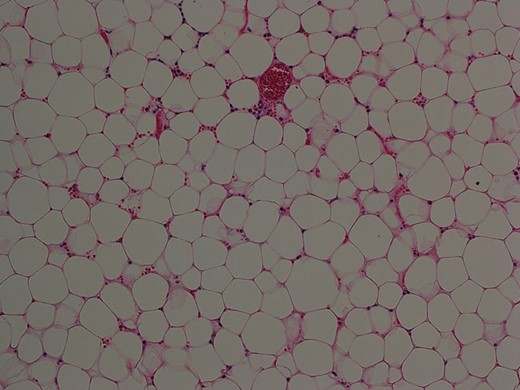

Macroscopically, the specimen was 80 × 60 × 25 mm in size and weighed 74.8 g. Histopathological examination revealed that the tumor was composed of mature adipocytes indistinguishable from normal adipose tissue, confirming that it was a lipoma (Fig. 3). Postoperative recovery was uneventful and the patient was discharged on postoperative day 5.

Histopathological examination of the resected specimen showed that the tumor was composed of mature fat cells (hematoxylin and eosin, original object magnification ×10).